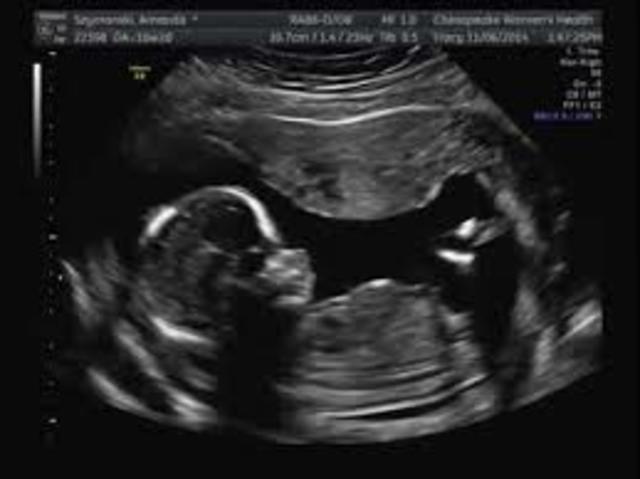

• Pregnancy at 11 & 12 weeks

Pregnancy at 11 & 12 weeks

Baby's starting to have sleeping patterns. Limbs are starting to grow faster than its head and it's starting to look more like a tiny person, also may be able to kick its feet. Genitals have developed fully. Has its own blood supply. Skin is thickening and vocal cords are beginning to form. Face is almost fully formed. Muscles are starting to respond to brain signals. Most people have miscarriages until 12 weeks. If you have a miscarriage by now it is because of a bacterial infection.